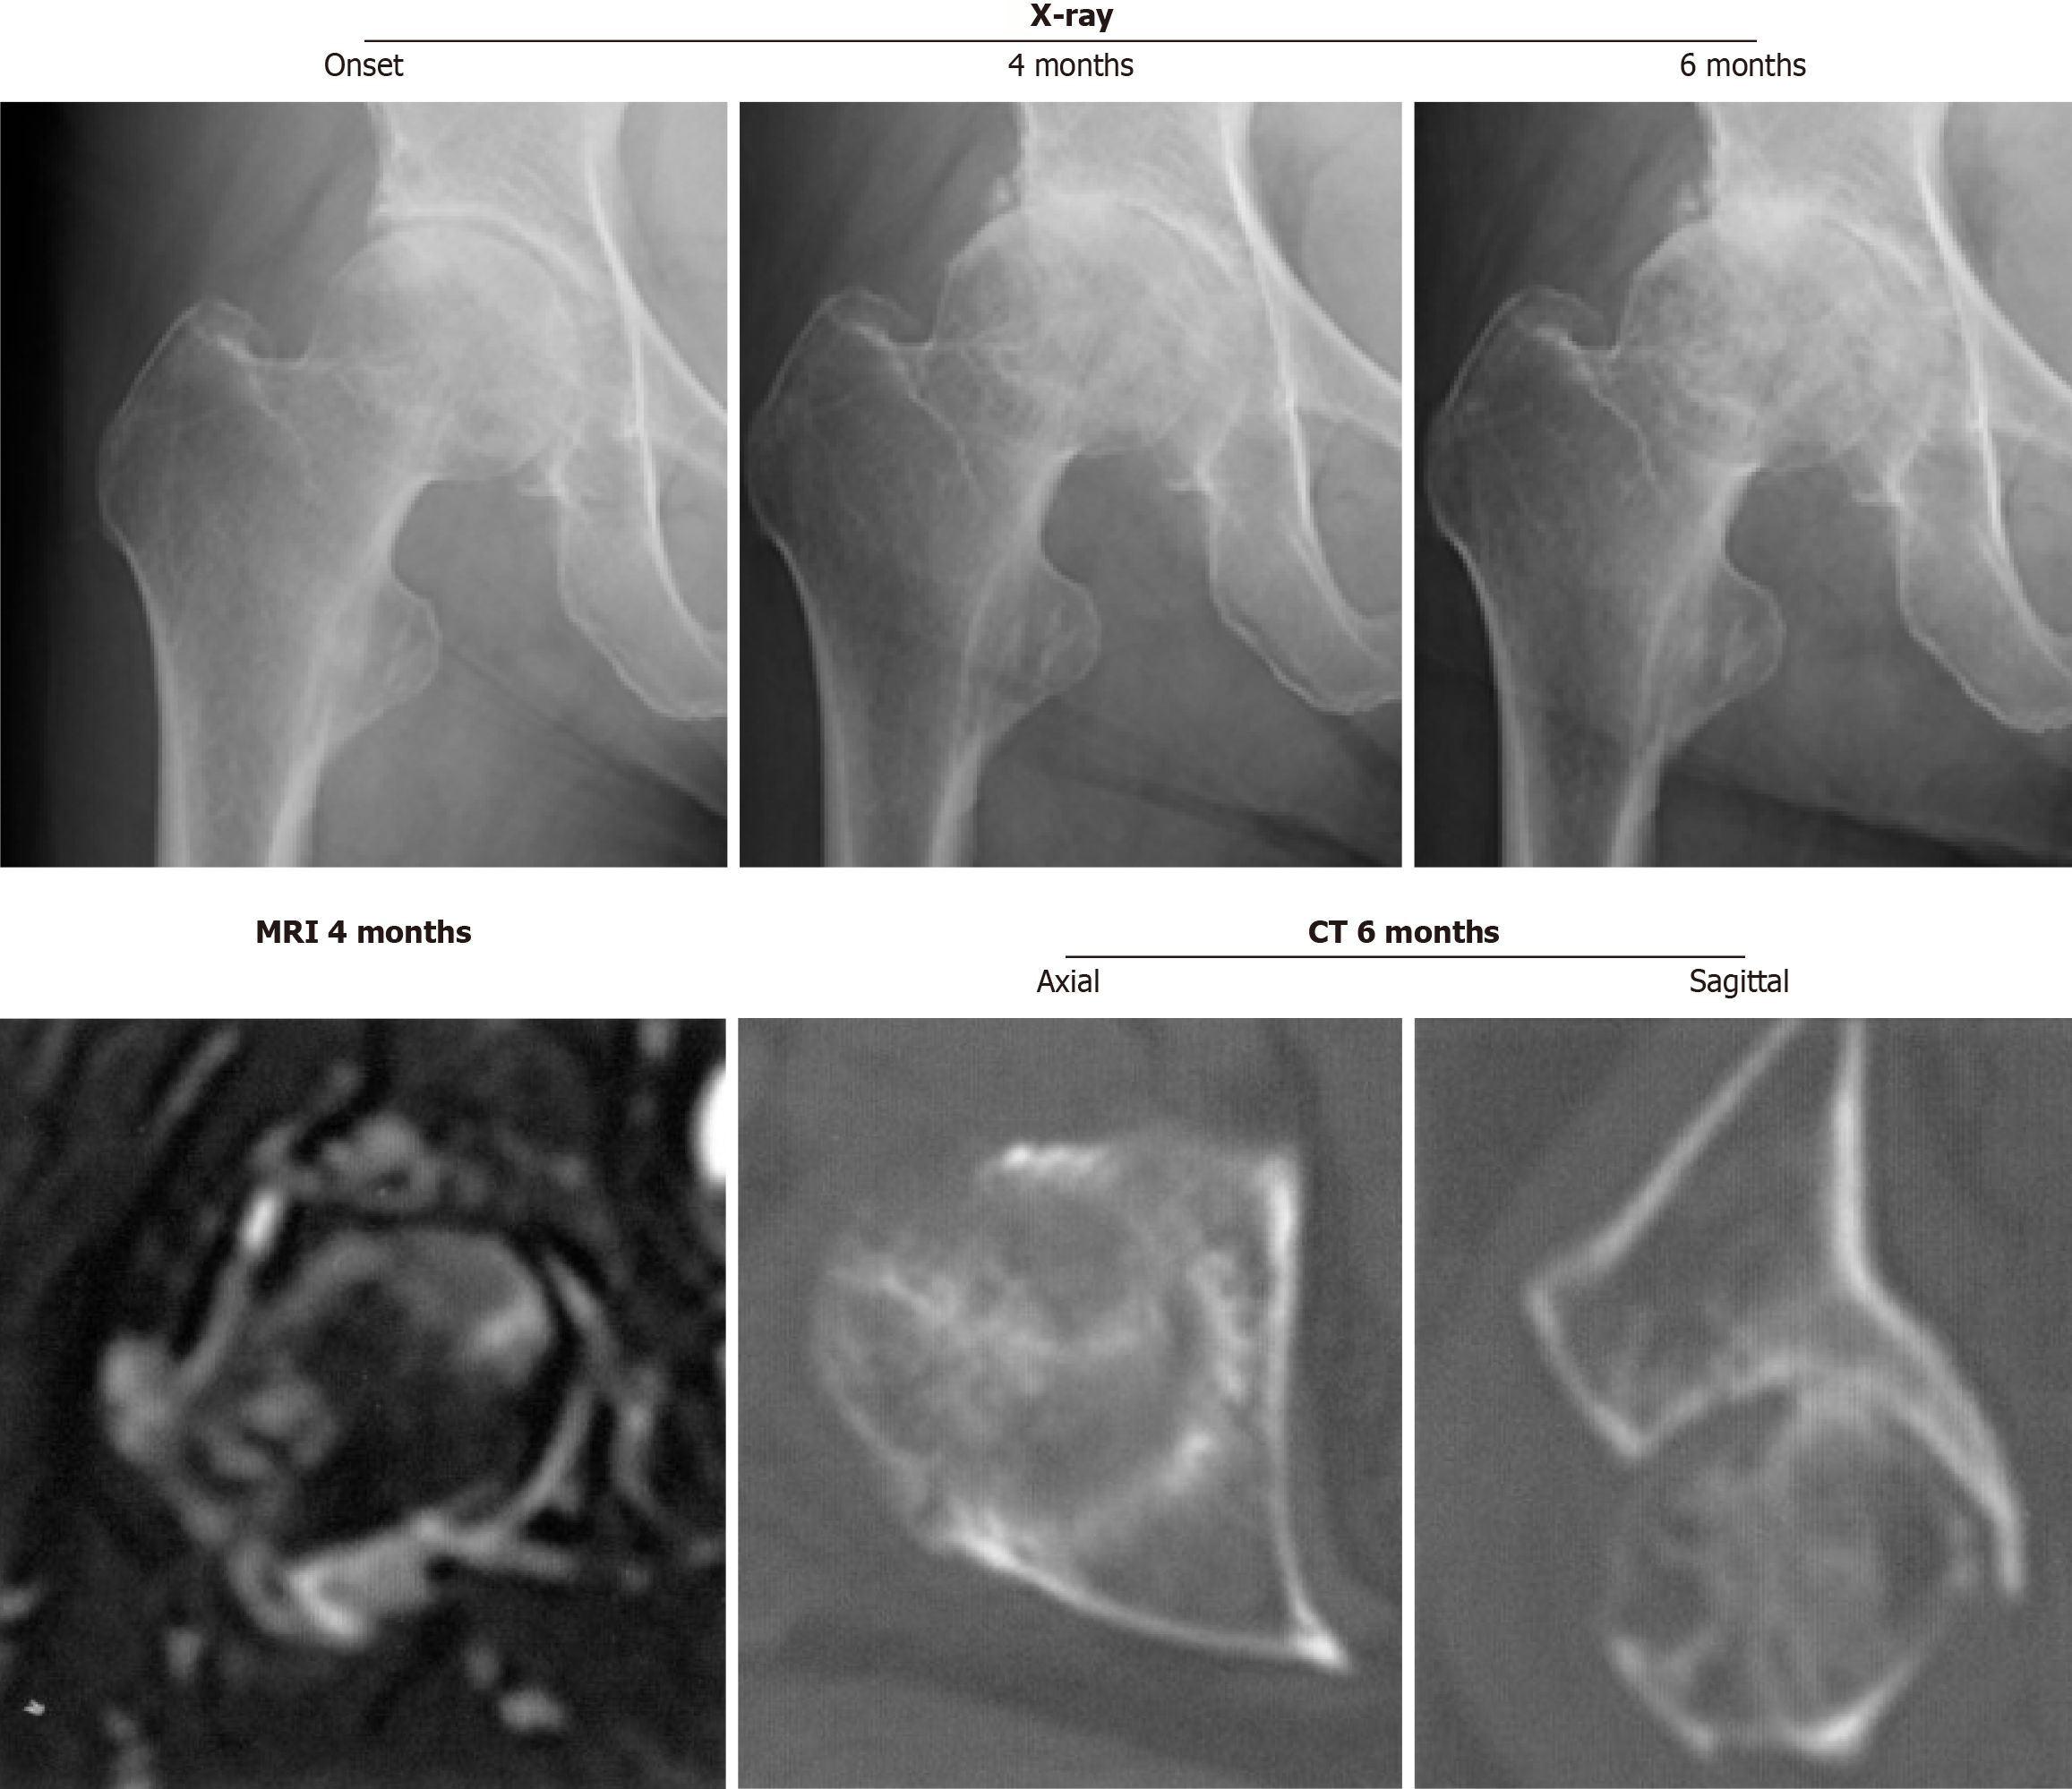

Figure 2 Right hip joint with rapidly progressive osteoarthritis of the hip demonstrating partial destruction of the anterior portion of the femoral head on computed tomography at 6 months after the onset subsequent to rapid chondrolysis.

Magnetic resonance imaging at 4 months after the onset shows high intensity on the short τ inversion recovery sequence image in the proximal femur, including the femoral neck and head. CT: Computed tomography; MRI: Magnetic resonance imaging.